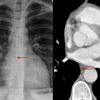

PA angio

Fig 1

Date: 03/23/2004

Views: 3656